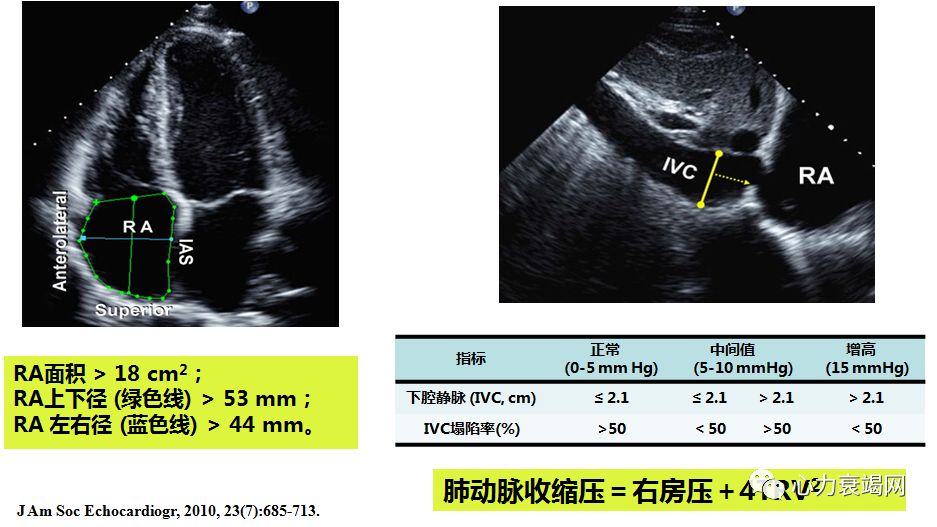

肺动脉压的评估